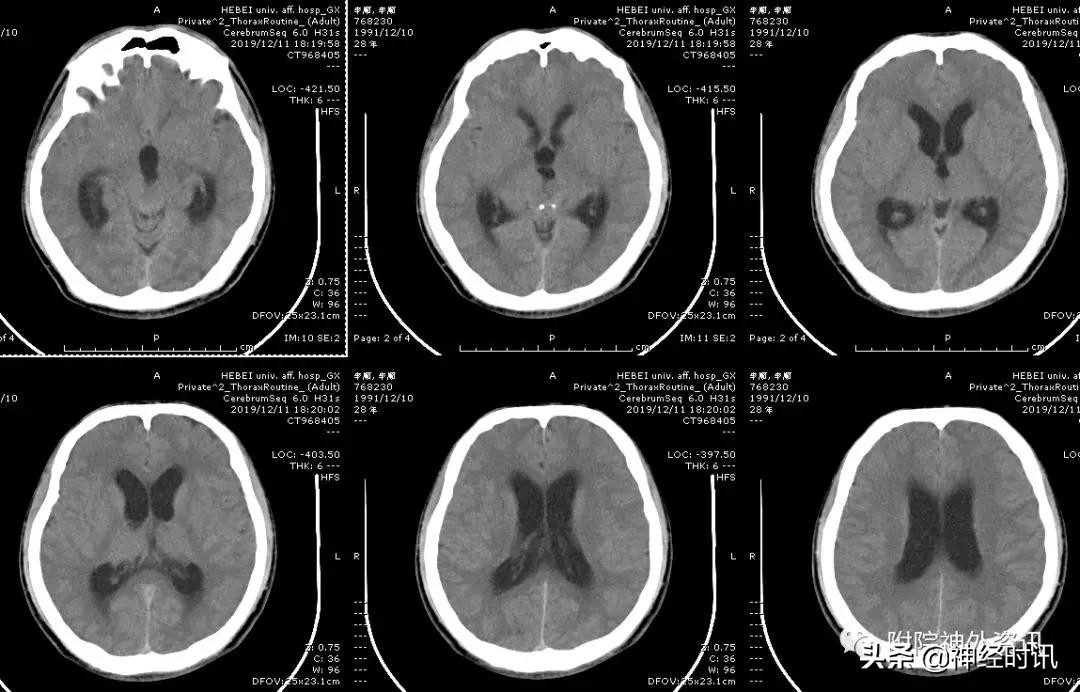

男性,28岁,主因复视20余天入院,查体双瞳孔不等大,直径左=3. 5mm,右=3.0 mm,对光反射迟钝,双眼上视困难,左眼眼位异常,向内下斜视。